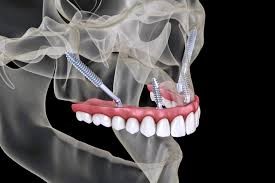

ایمپلنت های زیگوماتیک در اواخر دهه ۱۹۹۰ توسط دکتر پر اینگوار برانمارک (Per Ingvar Branemark) برای اولین بار به جهانیان معرفی شد. ایشان در سراسر جهان و جامعه پزشکی به عنوان پدر ایمپلنتولوژی دندان نیز شناخته می شود. ایمپلنت های زیگوماتیک یا زایگوماتیک در بیمارانی مورد استفاده قرار می گیرند که در بخش فوقانی و پشت فک خود بافت و تراکم کافی استخوان ندارند، و جایگزین ایمپلنت های معمولی دندان به شمار می روند. این ایمپلنت ها نسبت به ایمپلنت های معمولی تفاوت هایی دارند، زیرا نحوه قرارگیری پایه ایمپلنت زیگوماتیک با پایه ایمپلنت های معمولی متفاوت است. این ایمپلنت ها نسبت به ایمپلنت های دندانی معمولی بلندتر هستند و در لایه های استخوانی استخوان گونه که زیگوما نامیده می شود قرار می گیرند و پشتیبانی بیشتری را برای بیمارانی که دچار تحلیل شدید استخوان در استخوان گونه فک بالا هستند، فراهم می کنند. اما پایه ایمپلنت معمولی در فک بالا قرار می گیرد. این مسئله به این دلیل است که استخوان گونه نسبت به استخوان فک کیفیت و تراکم بیشتری دارد و بنابراین در بیمارانی که استخوان فک آنها تراکم کافی ندارد، استخوان گونه می تواند به عنوان بهترین جایگزین در نظر گرفته شود. ایمپلنت های زیگوماتیک برای اتصال دندان مصنوعی، مانند بریج دندان یا دندان مصنوعی، در فک بالا طراحی شده اند. ایمپلنت با جراحی در استخوان زیگوما قرار می گیرد که استخوانی محکم تر و متراکم تر از استخوان فک است و به آن اجازه می دهد وزن پروتز را تحمل کند.

لازم به ذکر است ایمپلنت های زیگوماتیک از جمله روش های دو مرحله ای کاشت ایمپلنت محسوب می شوند که حتی به صورت کاشت فوری نیز قابل انجام است. با توجه به اینکه پایه ایمپلنت به جای استخوان فک در استخوان گونه کاشته خواهد شد، بنابراین از کنار سینوس ها عبور می کند و در نتیجه طول این نوع ایمپلنت ها نسبت به سایر انواع ایمپلنت ها بیشتر خواهد بود. نکته حائز اهمیت دیگر این است که این ایمپلنت ها را می توان حتی پس از عفونت استخوان و پیوند استخوان نیز داخل دهان بیمار کار گذاشت و به همین دلیل به آنها ایمپلنت های نجات نیز گفته می شود.

در روش های معمول کاشت ایمپلنت های زیگوماتیک، یک ایمپلنت در هر طرف فک بالا قرار می گیرد. این ایمپلنت ها را می توان با ایمپلنت های دندانی سنتی در ناحیه جلوی فک ترکیب کرد، مشروط بر اینکه استخوان کافی در دسترس باشد. این توزیع به متعادل کردن نیروهای بایت کمک می کند و پشتیبانی بهینه ای برای دندان های ثابت فراهم می کند.